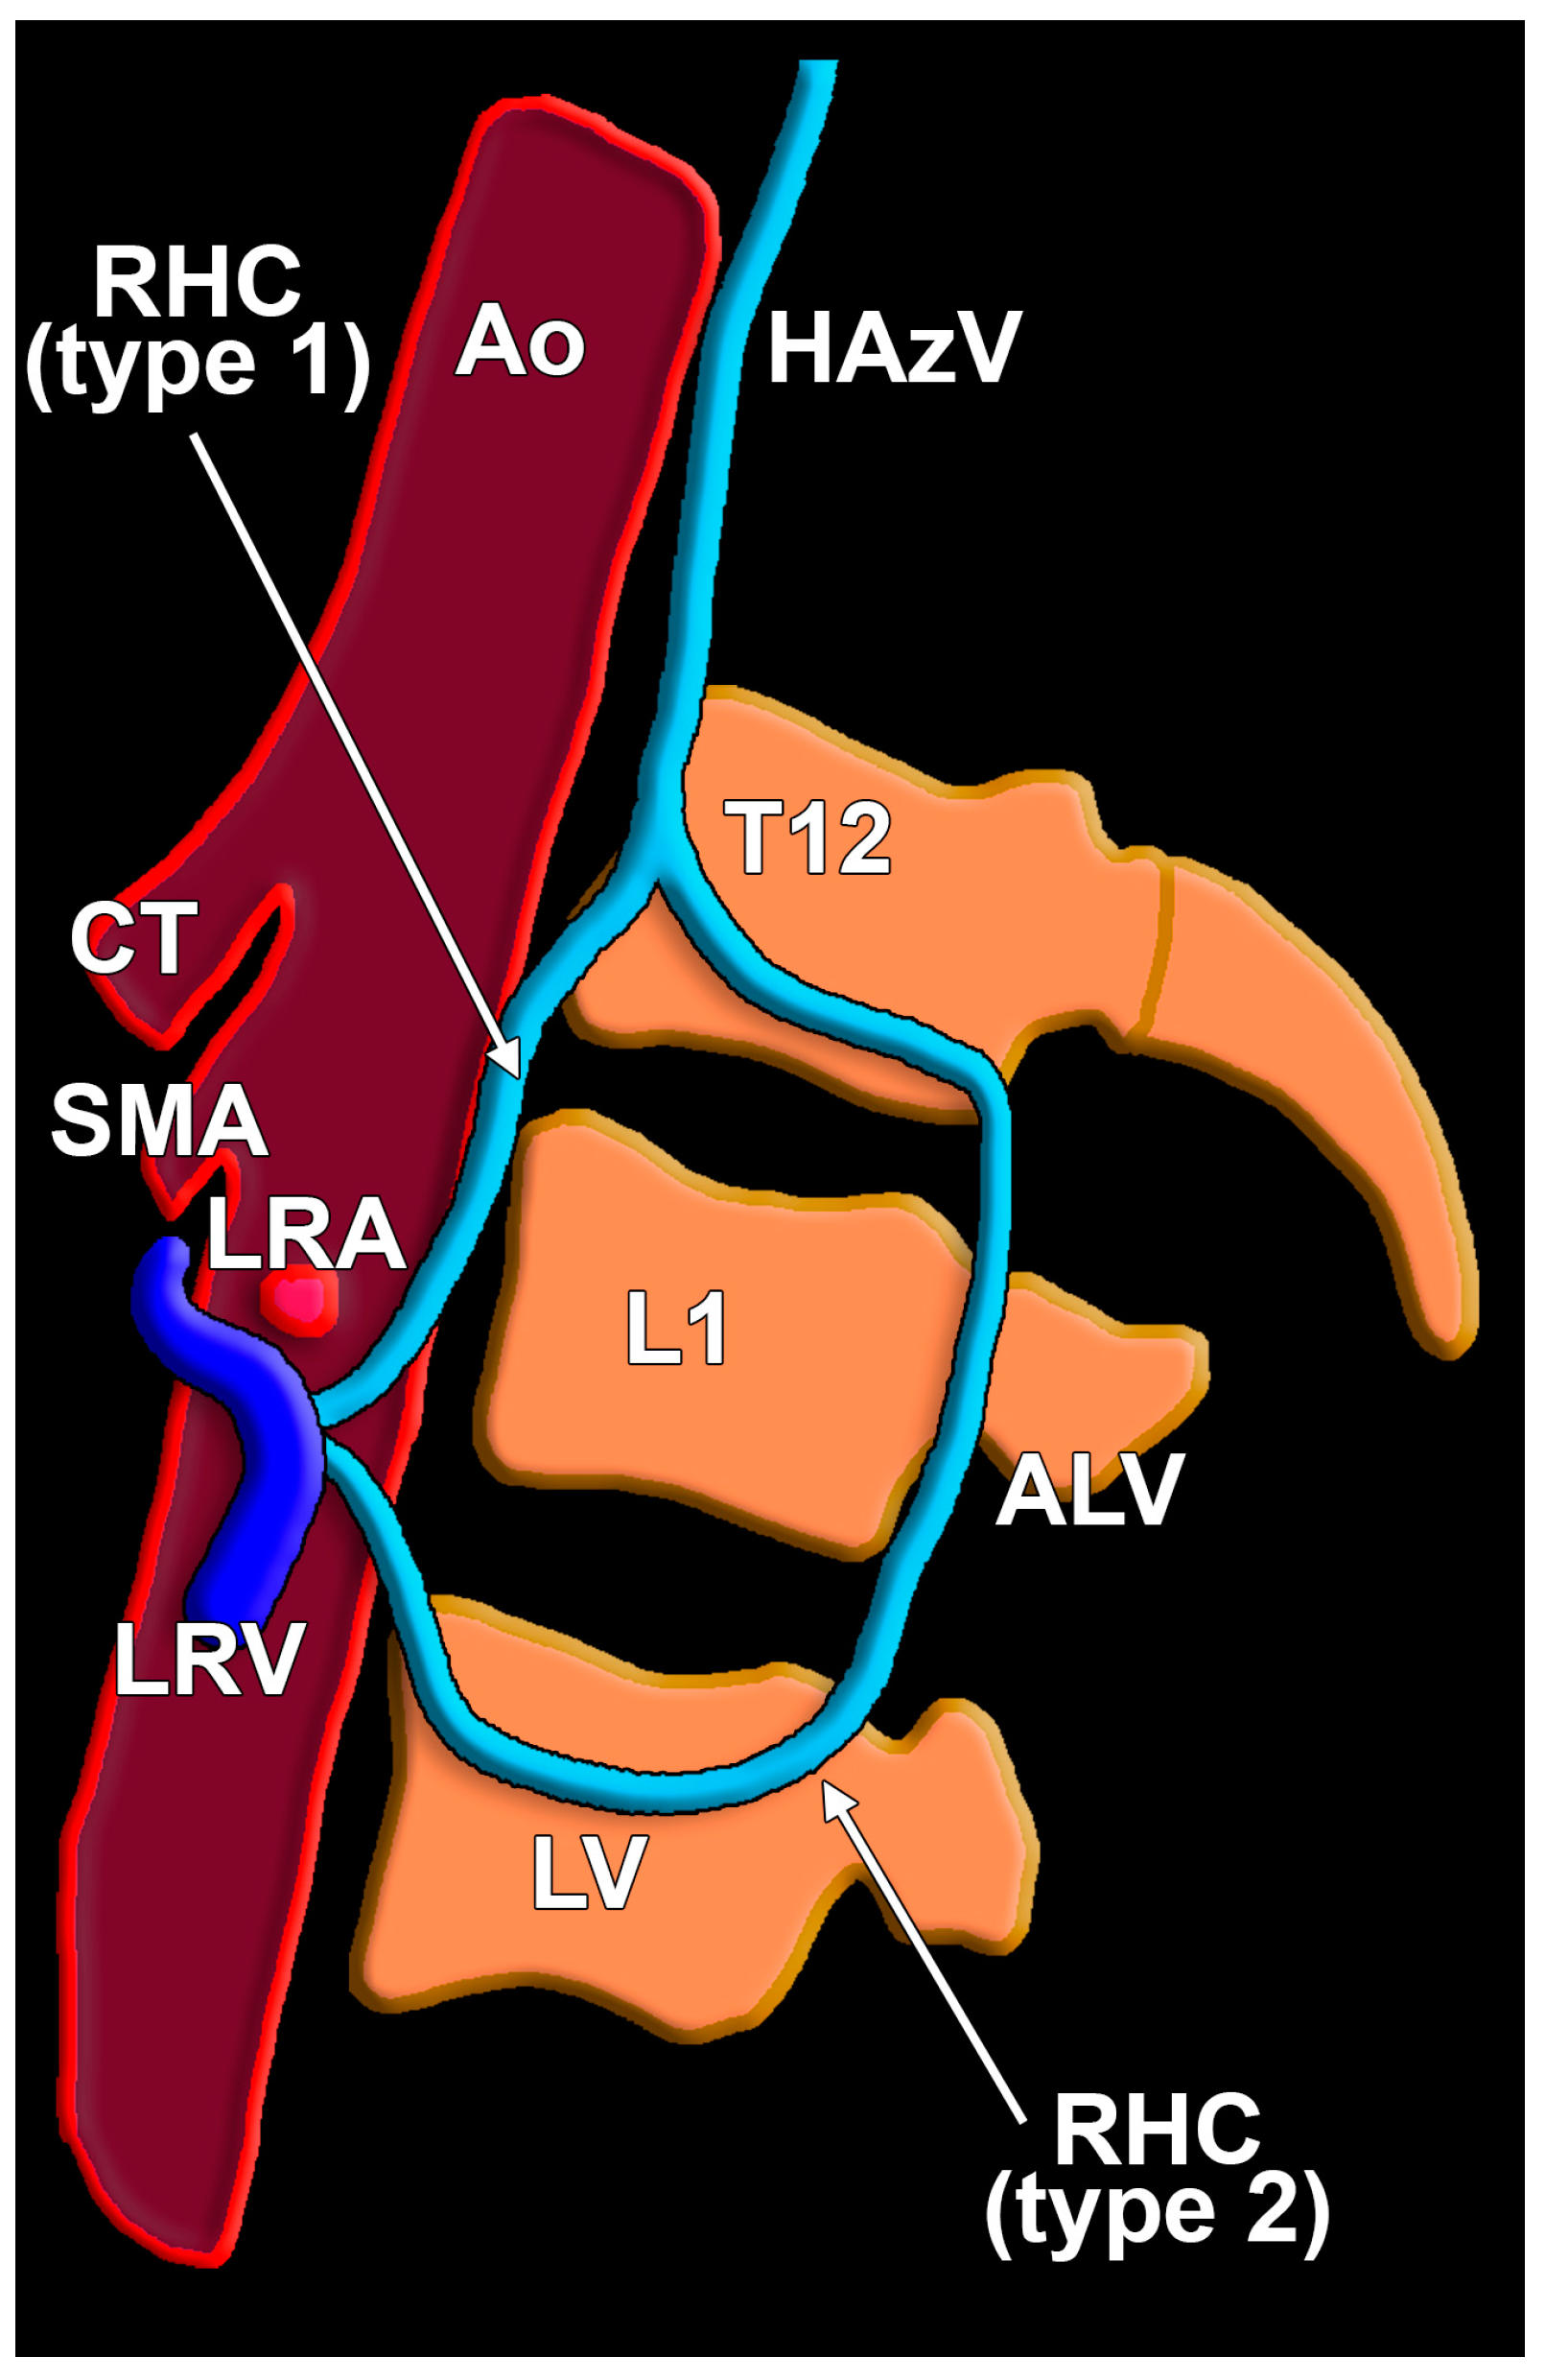

| ALV | ascending lumbar vein |

| HAzV | hemiazygos vein |

| LRV | left renal vein |

| RHC | reno-hemiazygos connection |

| RLRV | retroaortic left renal vein |

| Type 1 | Type 2 | |

|---|---|---|

| M | 2/4 (50%) | 2/4 (50%) |

| 2/85 (2.35%) | 2/85 (2.35%) | |

| F | 9/10 (90%) | 1/10 (10%) |

| 9/65 (13.84%) | 1/65 (1.53%) |

| LRV | LRV/RP | RLRV | CLRV | |

|---|---|---|---|---|

| Type 1 (11 cases) | 7 (63.64%) | 1 (9.09%) | 1 (9.09%) | 2 (18.18%) |

| Type 2 (3 cases) | 2 (66.67%) | – | – | 1 (33.33%) |

| L1/L2 Disc | L2 | L2/L3 Disc | L3 | |

| Type 1 (11 cases) | 1 (9.09%) | 5 (45.46%) | 3 (27.27%) | 2 (18.18%) |

| Type 2 (3 cases) | – | 1 (33.33%) | – | 2 (66.67%) |